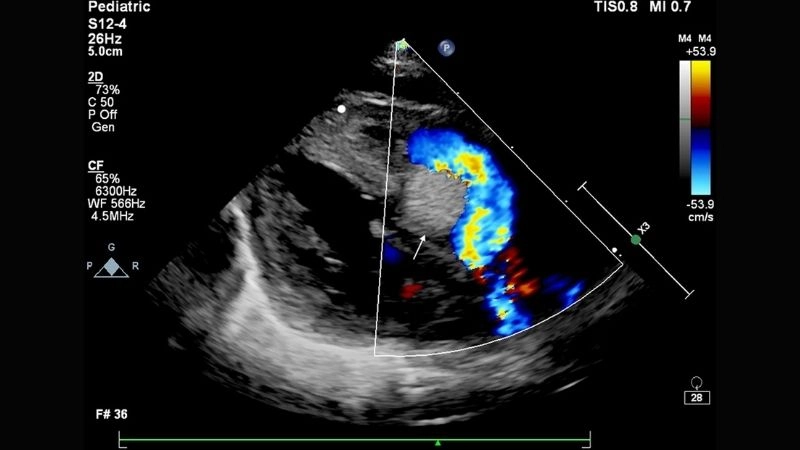

Images visual examples of rhabdomyoma

Rhabdomyoma is a rare benign tumor of striated muscle, commonly affecting the heart in children. Images often highlight cardiac masses that disrupt heart rhythm and function.

Real cases of rhabdomyoma in children hearts